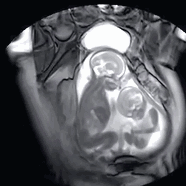

这是正在妈妈肚子里打架的你和你的兄弟。